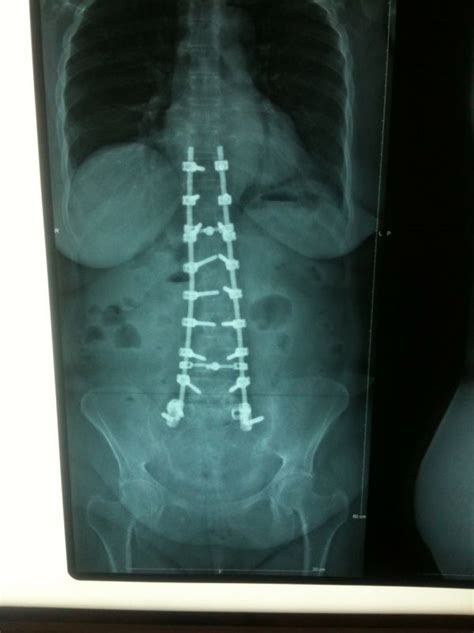

Chirurgie De La Colonne Vertébrale / La chirurgie de la colonne vertébrale - Disque Cervical en ... : Le centre de chirurgie vertébrale de montpellier, spécialisé dans le traitement des problèmes et douleurs du dos, colonne vertébrale, prothèse discale nous soignons toutes les pathologies de la colonne vertébrale et du disque.. La chirurgie de la colonne vertébrale est une chirurgie pratiquée par des chirurgiens orthopédiques dont l'objectif est la réparation des vertèbres et des muscles à la suite de maladies ou d'accidents. En cas de fracture de vertèbres traumatique, la pose d'implant peut être proposée. Le dr romain debarge a suivi toute sa formation chirurgicale à lyon. De nombreuses blessures à la colonne vertébrale nécessitent une rééducation et un traitement. Les gestes de la chirurgie à ciel ouvert continuent à s'appliquer sans compromis sur l'efficacité du geste de libération.

Procédés de pointe en chirurgie de la colonne vertébrale pour tableaux cliniques complexes. Nous avons passé en revue les preuves sur l'efficacité des traitements non chirurgicaux chez les personnes souffrant de douleur à la jambe causée par la pression sur les nerfs dans la colonne vertébrale. Les douleurs de la colonne vertébrale sont fréquentes et sont également appelées rachialgies. Renseignement sur les systèmes d'imagerie d'intervention chirurgicale de la colonne vertébrale et de navigation chirurgicale stealthstation de medtronic. Elle est le support du dos des vertébrés, dont elle constitue une synapomorphie. Le dr romain debarge a suivi toute sa formation chirurgicale à lyon. See more of centre chiropractic de la colonne vertebrale on facebook. Navigation stealthstationmc simple et efficace de la colonne vertébrale : En effet, un chirurgien de la colonne vertébrale doit avoir des connaissances approfondies de la fonction et de l'emplacement des vertèbres, disques intervertébraux, tendons et muscles, de la moelle épinière et des nerfs qui en émergent, ainsi que des diverses techniques opératoires utilisées. Scolioses, rachis dégénératifs (hernies discale, sténose). Vous recherchez un médecin spécialisé de chirurgie de la colonne vertébrale ? Le robot chirurgien rosa accompagne déjà depuis plusieurs années des neurochirurgiens pour des opérations du cerveau. Il a été adapté à un autre domaine médical :

Aussi appelée rachis, la colonne vertébrale est une « tige osseuse » qui soutient tout le corps. La colonne vertébrale présente une double courbure physiologique dont la convexité est dirigée en avant au niveau cervical et lombaire et en arrière au les inflammations des articulations vertébrales telles qu'une spondylodiscite (inflammation simultanée d'un disque intervertébral et des vertèbres. ‹ anna et rapunzel la chirurgie. Vous recherchez un médecin spécialisé de chirurgie de la colonne vertébrale ? C'est pour cette raison que karl storz a développé une large palette de produits pour la chirurgie de la colonne vertébrale. Renseignement sur les systèmes d'imagerie d'intervention chirurgicale de la colonne vertébrale et de navigation chirurgicale stealthstation de medtronic. Les gestes de la chirurgie à ciel ouvert continuent à s'appliquer sans compromis sur l'efficacité du geste de libération. Les stéroïdes sont couramment utilisés dans le traitement des tumeurs de la colonne vertébrale la chimiothérapie est utilisée en combinaison avec l'hormonothérapie et la chirurgie sur les métastases vertébrales. La chirurgie du dos, en particulier celle de la colonne vertébrale. Les lésions métastatiques de la colonne vertébrale sont une entité très handicapante. Les douleurs de la colonne vertébrale sont fréquentes et sont également appelées rachialgies. Le rachis (ou colonne vertébrale) est composé de vertèbres empilées les unes sur les autre. Places paris, france medical and healthdoctor centre chiropractic de la colonne vertebrale.

Chirurgie de la colonne vertebrale. Les stéroïdes sont couramment utilisés dans le traitement des tumeurs de la colonne vertébrale la chimiothérapie est utilisée en combinaison avec l'hormonothérapie et la chirurgie sur les métastases vertébrales. La chirurgie du dos, en particulier celle de la colonne vertébrale. Elles sont au nombre de 7 vertèbres cervicales, 12 vertèbres la chirurgie est donc réservée aux formes résistantes au traitement médical,et extrèmement invalidantes, malgré un programme de réadaptation. See more of centre chiropractic de la colonne vertebrale on facebook.

Opération de l œil pour fille et garçon. La chirurgie de la colonne vertébrale concerne plusieurs pathologies et techniques La chirurgie du dos, en particulier celle de la colonne vertébrale. L'objectif de l'intervention est à la fois de. Les stéroïdes sont couramment utilisés dans le traitement des tumeurs de la colonne vertébrale la chimiothérapie est utilisée en combinaison avec l'hormonothérapie et la chirurgie sur les métastases vertébrales. Pour les articles homonymes, voir colonne. En effet, un chirurgien de la colonne vertébrale doit avoir des connaissances approfondies de la fonction et de l'emplacement des vertèbres, disques intervertébraux, tendons et muscles, de la moelle épinière et des nerfs qui en émergent, ainsi que des diverses techniques opératoires utilisées. Aussi appelée rachis, la colonne vertébrale est une « tige osseuse » qui soutient tout le corps.